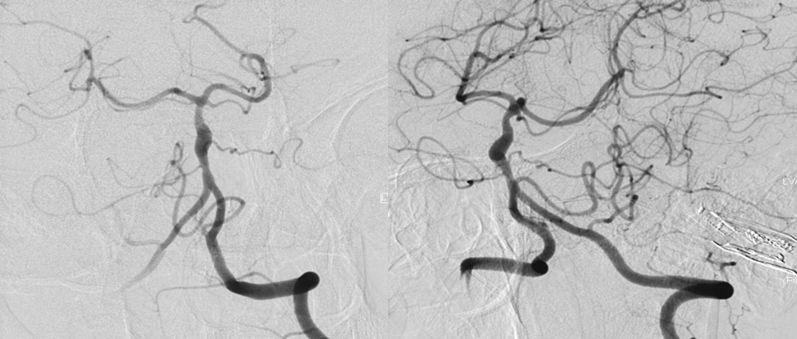

本院DSA:基底动脉巨大夹层动脉瘤,双侧后交通动脉未见明显开放(图6)。

图6